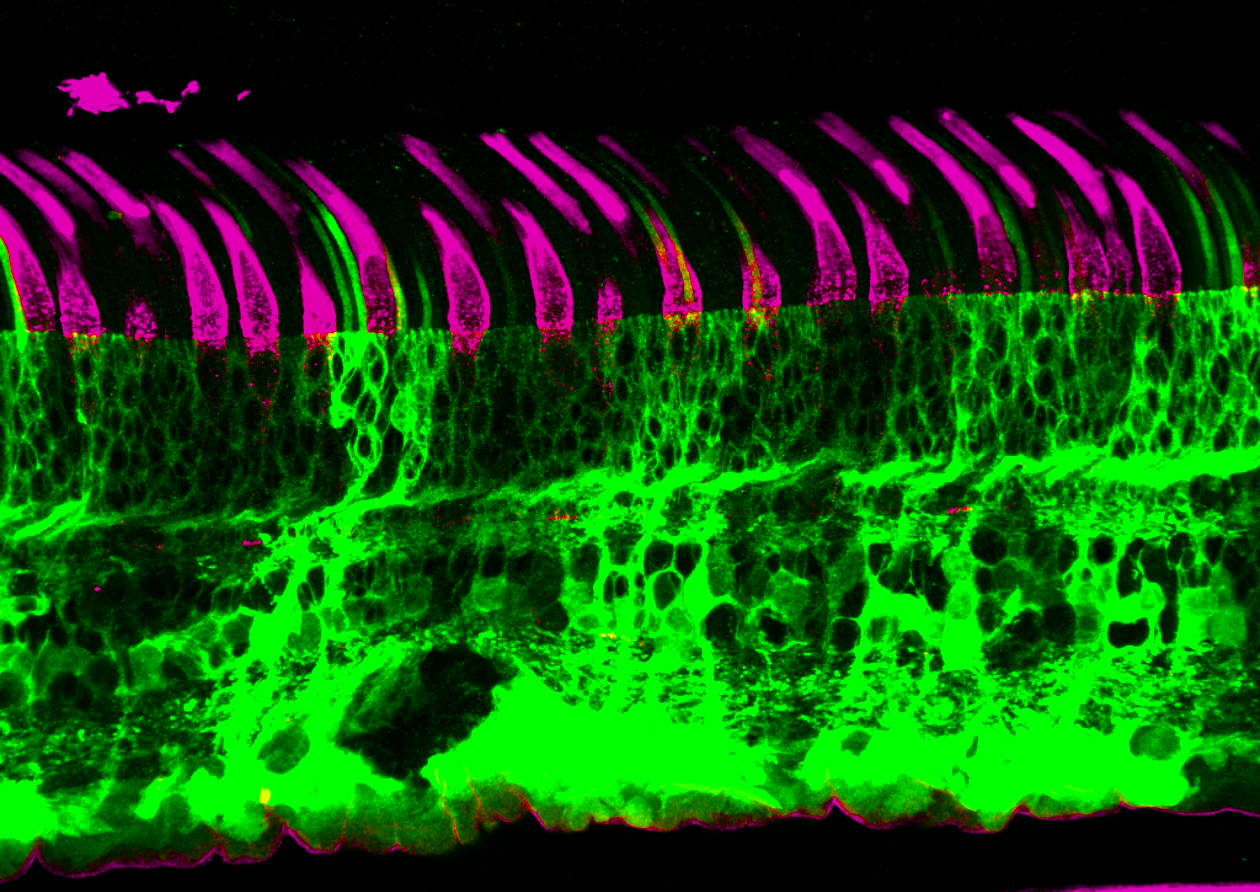

Retina

ATX002

Optimized for intravitreal delivery, producing strong pan-retinal expression across all regions of the retina, including fovea and periphery. 14x increase in cells transduced compared to clinical-stage 7m8. 24x increase in cells transduced compared to AAV2.

Fluorescent microscopy image of a retinal cross-section transduced by AAVs expressing GFP.